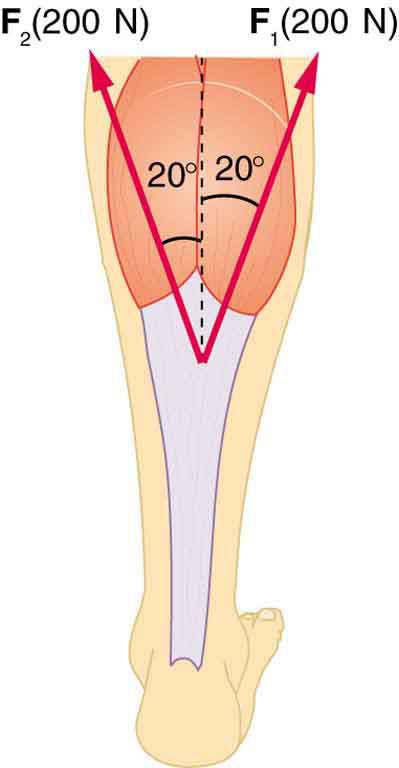

Two muscles in the back of the leg pull on the Achilles tendon, as shown in Figure 9.38. What total force do they exert?